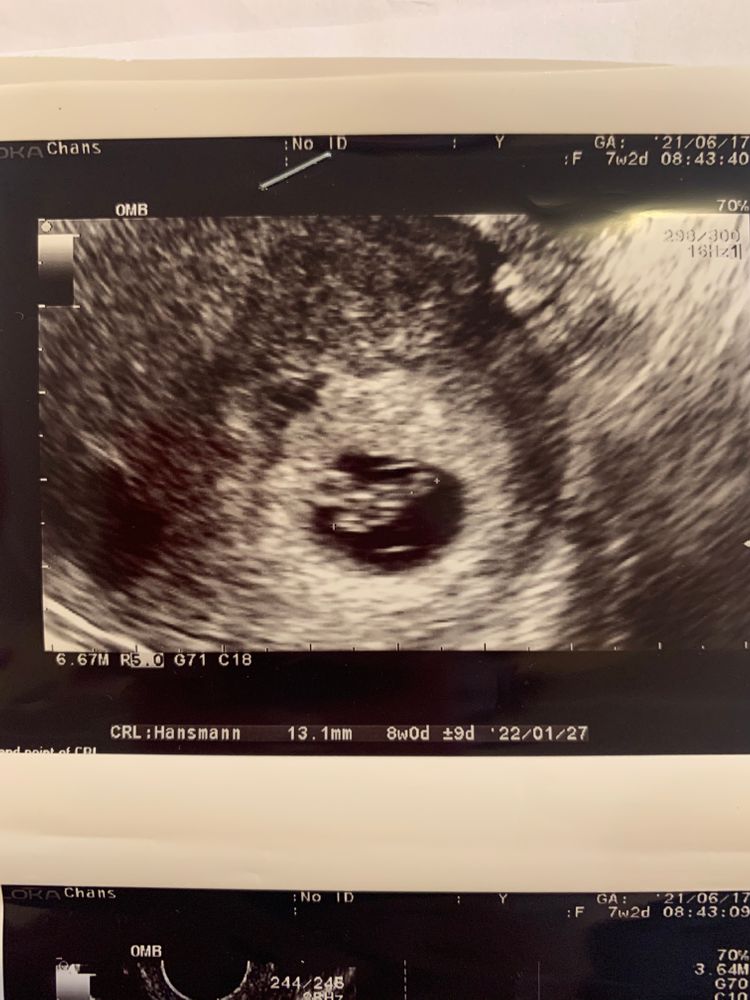

8+1 недель УЗИ

Изображение Kate Agaeva, вот нашла, 13.8 мм. Сказала начали появляться зачатки ручек и ножек) Зачатки, а ваша узистка уже прям человечка хотела увидеть🤦🏻‍♀️ Так что все хорошо у Вас), не переживайте

Так ведь еще рано для человечка :) а 4 дня - это вообще не отставание (может даже погрешность узи). Когда ваш малыш подрастет, то будет и такое, что в какие-то недели головка опережает, поиом животик, потом нога и т.п. Не стоит переживать, малыши растут скачками. Вполне возможно, что ваш уже сегодня нагнал и перегнал эти 4е дня.

Да не сильно отстает! У меня когда ктр 13 мм был мне срок по узи поставили 7+5 . Не переживайте! Все хорошо! Малыш ваш красавчик! Догонит и перегонит всех🥰